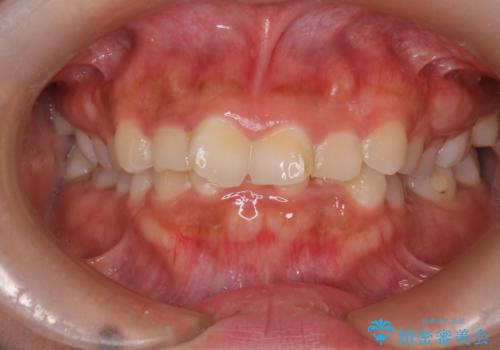

[セラミック治療] 前歯の審美治療に伴う矯正治療